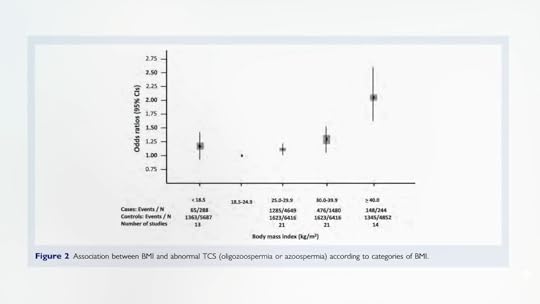

Back to the ABCs of obesity’s health consequences, F is for Fertility—or rather failed fertility. “Overweight and obese persons seeking fertility should be educated on the detrimental effects of fatness and the benefits of weight reduction, including improvement in pregnancy rates,” one meta-analysis concluded. Men also may suffer impaired fertility. The heavier a man is, the greater his risk of having a low sperm count or being completely sterile, as you can see below and at 3:01 in my video. This may be due in part to the effects of excess body fat on testosterone levels.